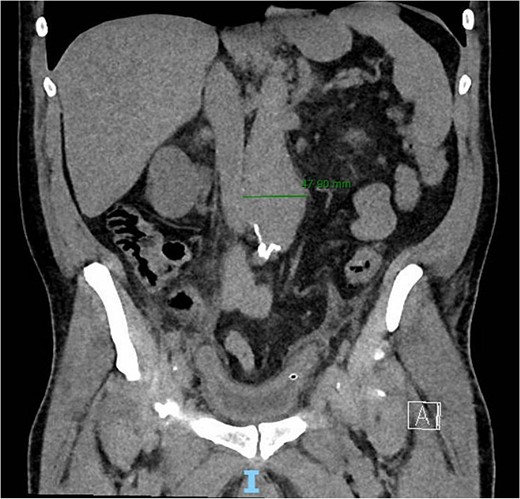

A 56-year-old male with no reported past medical history and a 70 pack year smoking history presented with a chief complaint of lower abdominal pain and body aches. On presentation, the patients white blood cell count (WBC) was 39.6 and procalcitonin was 43.4. Blood cultures were drawn and demonstrated P. mirabilis bacteremia. Computed tomography (CT) abdomen/pelvis was performed as well as ultrasound (US) of scrotum demonstrating a complex fluid collection within scrotal sac that was determined to be a scrotal wall abscess. The patient was started on a course of Unasyn and Urology promptly took him to the operating room (OR) for incision and drainage. Vascular surgery was consulted due to an incidental finding of an abdominal aortic aneurysm on CT measuring 4.7 × 4.6 cm (Figs 1 and 2). The patient was evaluated by the vascular surgery team following his urological procedure and denied any history of abdominal pain or back pain. Physical exam was largely unremarkable however the patient’s bilateral toes were noted to have blue discoloration with motor and sensation intact. Outpatient follow up with routine US scans for the AAA was recommended. Ankle brachial index (ABI) as well as an echocardiography was ordered to further work up the patient’s dusky toes. On Day 2 of hospitalization, ABIs returned showing severe peripheral vascular disease (PVD) and the echocardiography ruled out endocarditis. At this time an angiogram was planned to further the patient’s PVD workup however this was deferred as the patient remained septic with a WBC of 30. Over the course of the next few days the patient refused antibiotics and remained septic with a WBC in the 20s. At this time his toes quickly deteriorated from dusky to dry gangrene. On Day 8 of hospitalization the patient remained septic and was now complaining of new onset mid-abdominal pain. Emergent CT showed AAA was now 7.7 × 7.8 cm with periaortic fat stranding concerning for impending rupture (Figs 3 and 4). The patient was taken emergently to the OR for open repair. Upon visualization, the abdominal aortic aneurysm was clearly infected with signs of impending rupture on the left lateral wall and purulent material including infected thrombus. Tissue was cultured however showed no growth, likely due to the fact that the patient had been on antibiotic therapy for a week at this time. Reconstruction with an aorto-biiliac bypass using rifampin-soaked dacron graft was performed. A piece of omentum was mobilized over the graft and the retroperitoneum was closed over it. The abdomen was left open for a return to the OR for a second look which showed no concerns for bowel ischemia, worsening infection or bleeding. On post-op Day 5 the patient was extubated, off pressor support, and transferred to the floor. The patient’s postoperative course was unremarkable except for bilateral toes demarcating to dry gangrene.

Frontal CT of the abdomen and pelvis demonstrating 4.79 cm AAA.